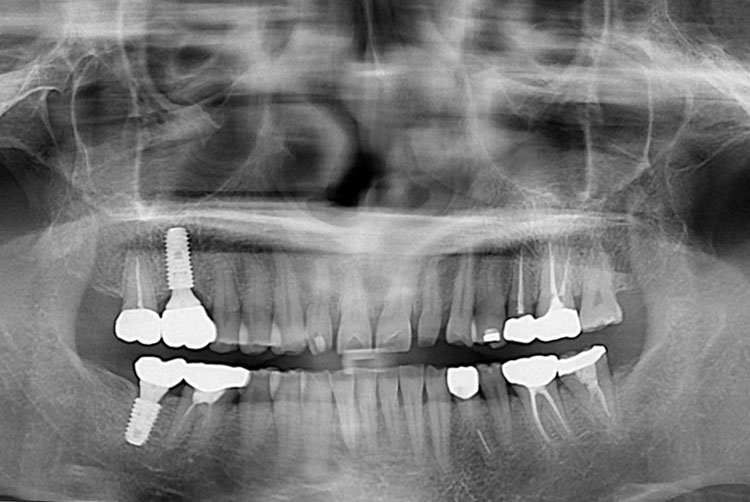

[임플란트] 임플란트

치료후 : 2016-08-19

세종치과는 많은 환자와 다양한 케이스를 바탕으로 항상 편안한 임플란트 수술을 제공하고자 노력하고,

오래동안 튼튼히 쓸 수 있는 임플란트 수술을 가장 큰 목표로 삼고 있습니다.